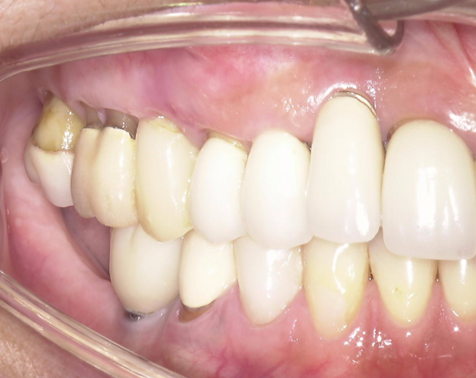

①歯根破折により右上小臼歯が動揺し、歯肉が腫れてしまい、周囲の歯槽骨が吸収していてインプラント埋入

が出来ないと他院で診断され、当院にインプラント治療を希望されました。